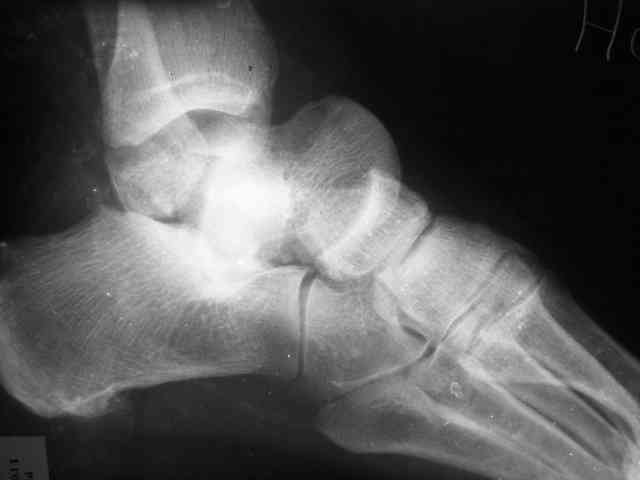

Уважаемый Александр! Как обещал представляю Р-граммы и операционные фото.

При столь массивном секвестре (блок таранной кости), длительная антибиотикотерапия только губит естественную флору и помогает селекции

Стабильность дает возможность расти сосудам. При хорошем кровоснабжении смежных фрагментов это все, что надо. А здесь есть большой секвестр. Разумно ли ждать, пока он васкуляризуется? Очевидно, без некрэктомии проблему не решить.